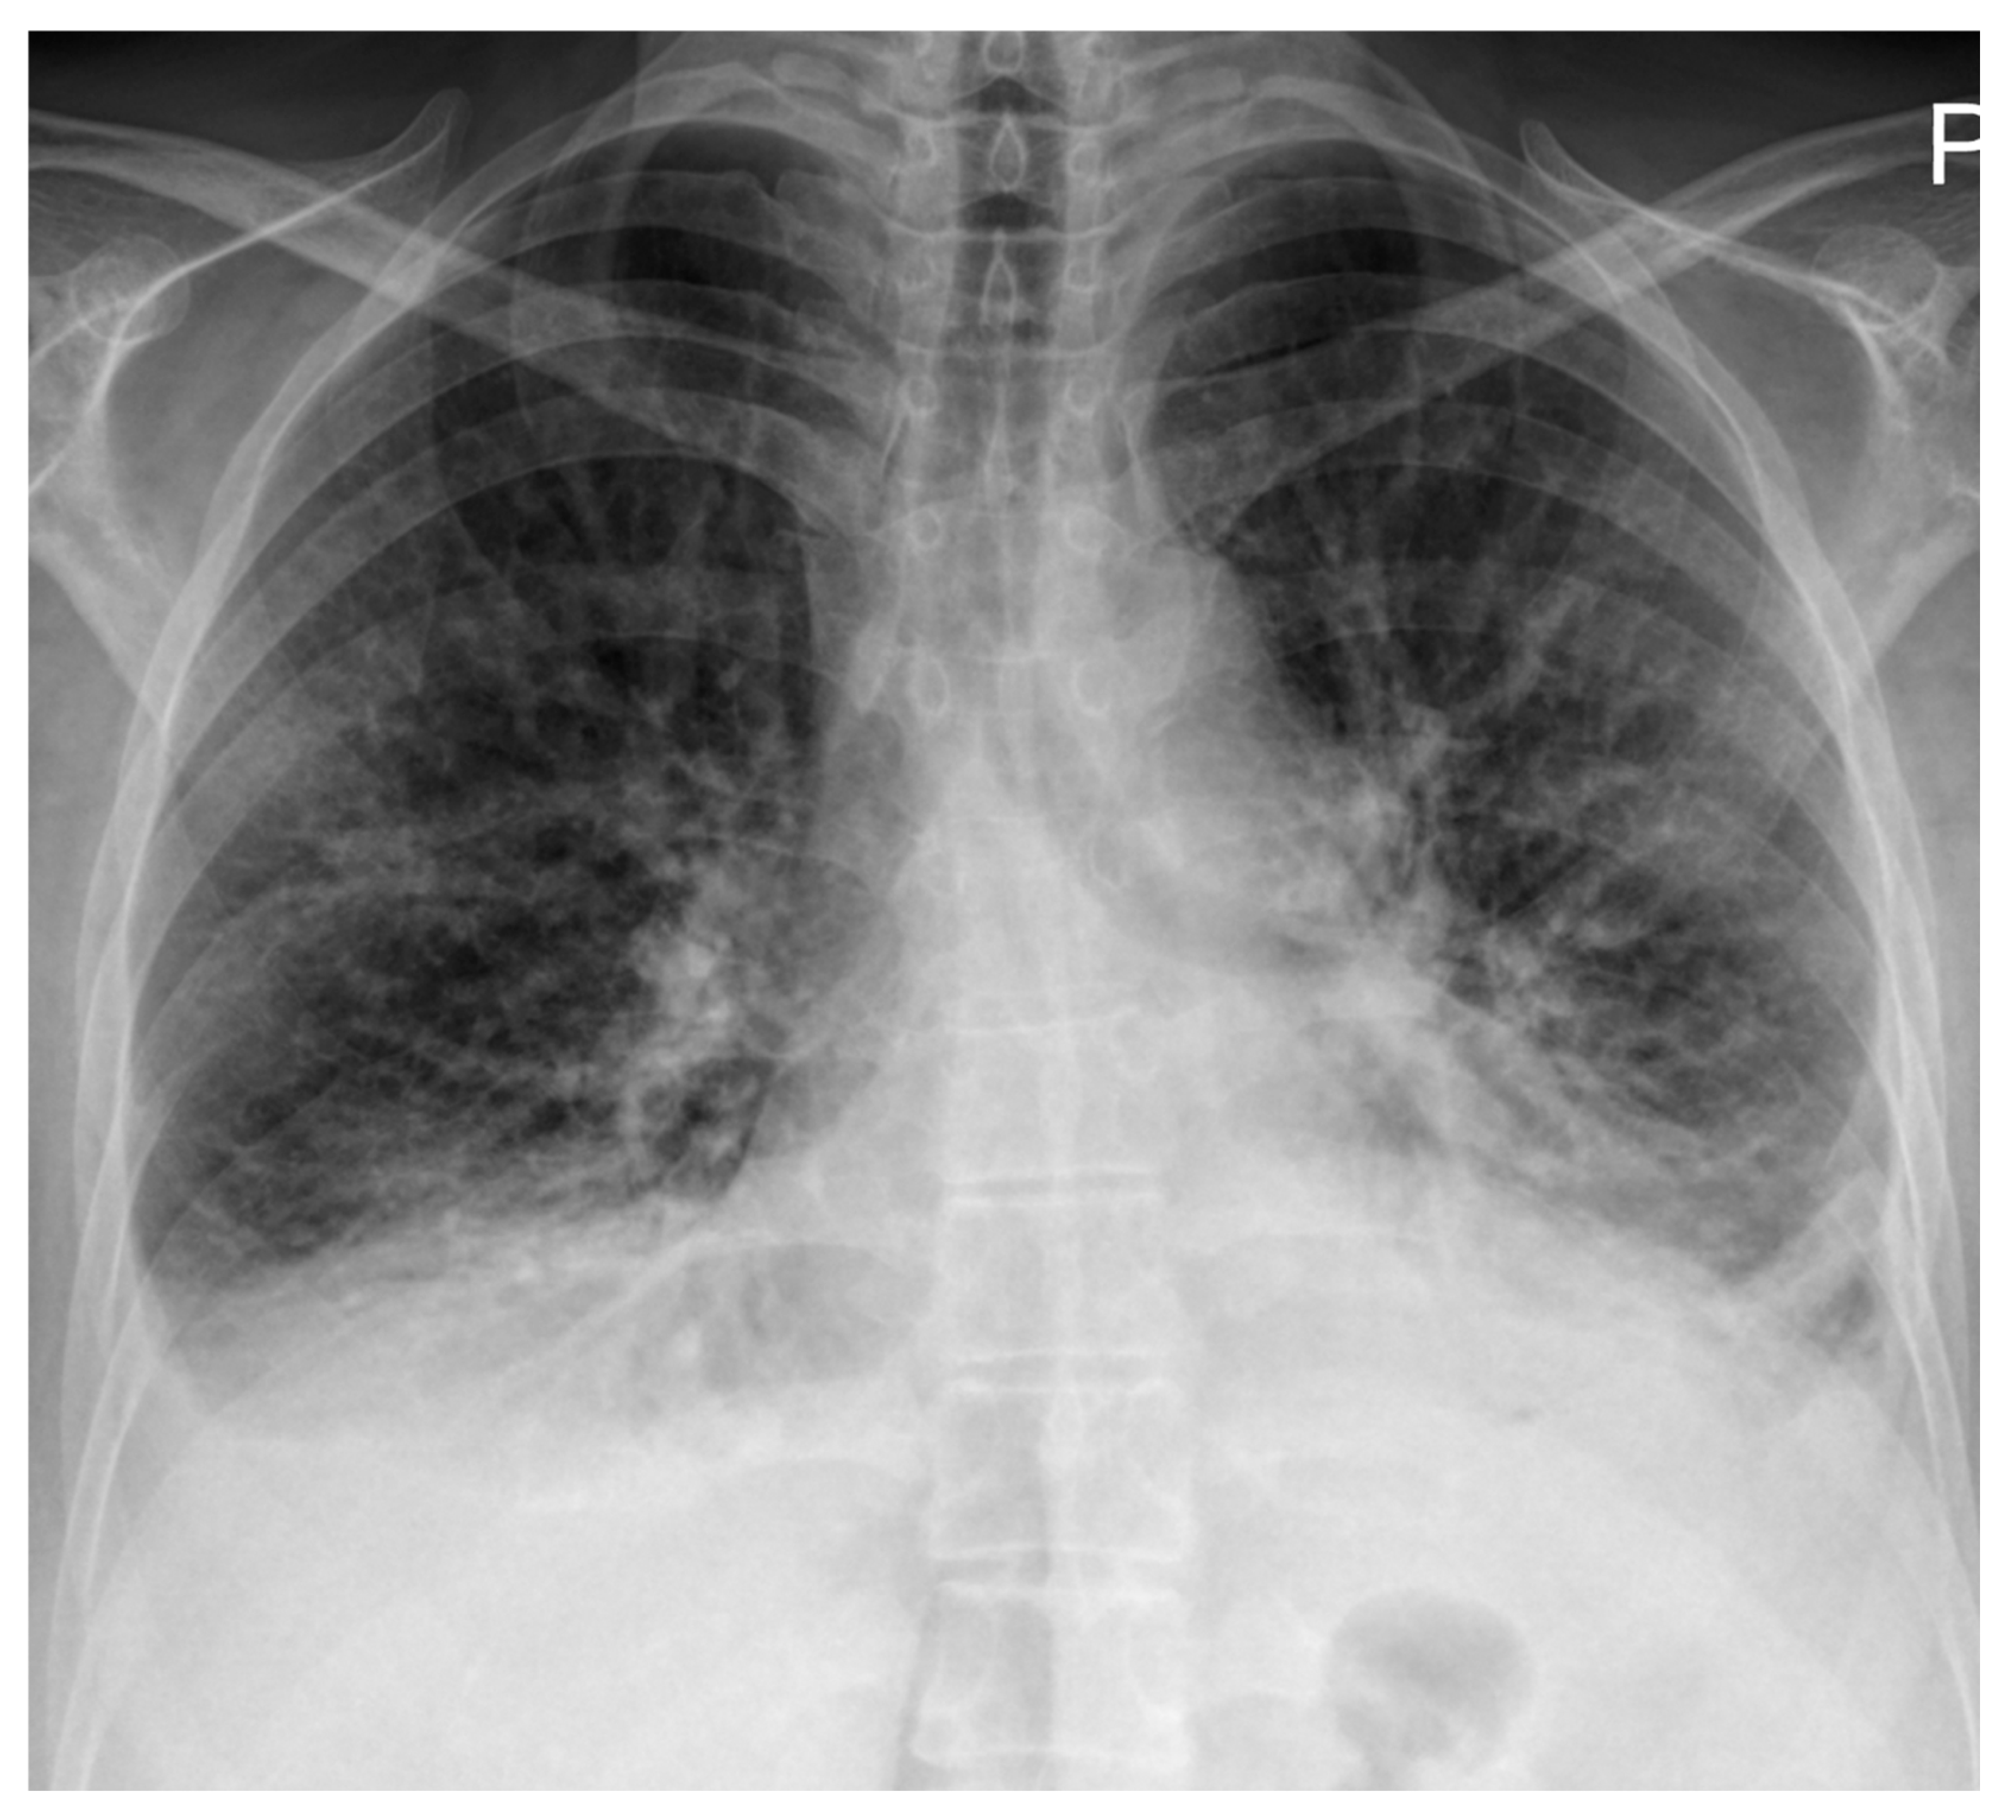

High-resolution computed tomography (HRCT) (Figure 2) showed markedly dilated pulmonary arteries, a small pericardial effusion, and absence of interstitial lung disease or features of pulmonary veno-occlusive disease. The “egg-and-banana sign” was observed (Figure 2D), with the main pulmonary artery appearing enlarged and ovoid (‘egg’) above the aortic arch (‘banana’), a pattern typically seen in pulmonary hypertension.

Figure 2.

High-resolution computed tomography. (A) Normal lung parenchyma. (B) Small pericardial effusion (orange arrow). (C) Dilated main pulmonary artery measuring 30.7 mm (normal <27 mm in females). (D) The “egg-and-banana sign” in pulmonary hypertension: the dilated pulmonary artery (blue arrow, ‘egg’) seen above the lower margin of the aortic arch (green arrow, ‘banana’).